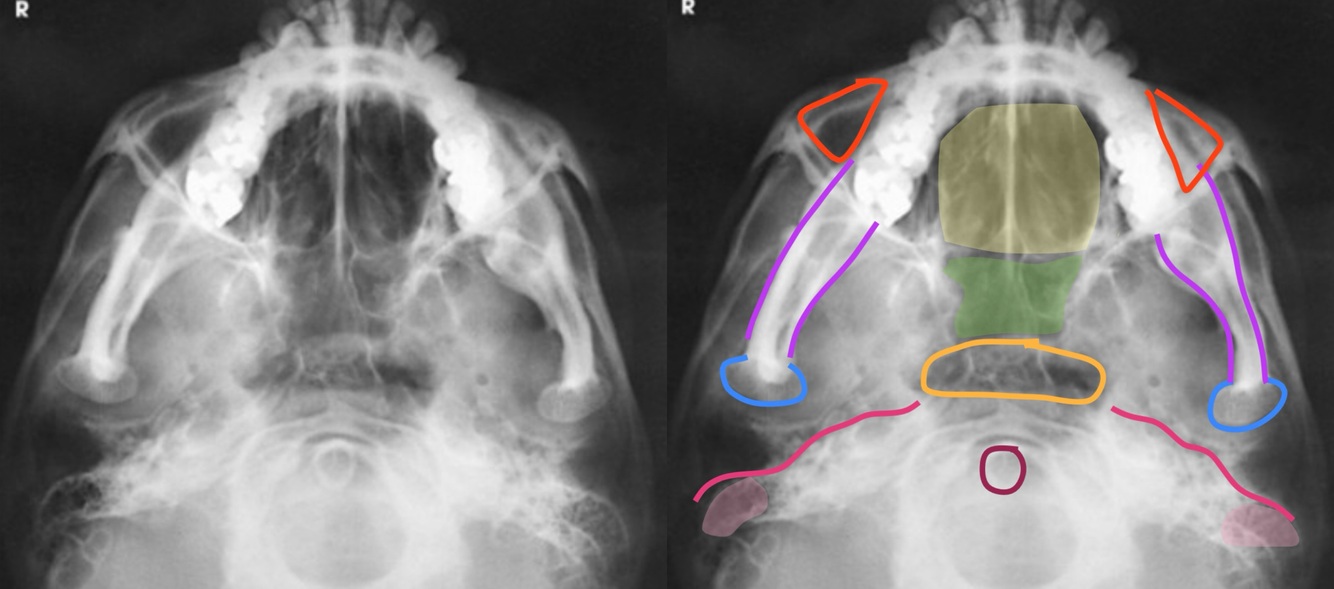

SUBMENTOVERTICAL (SMV) Positioning

A

-MSP is ⟂ to IR

-IOML is II to IR

-CR: Enters the MSP of the throat between the gonions

⟂ to IOML

⟂ to sella turcica

3/4” anterior to the EAM

-Respiration: Suspend

22

Q

SUBMENTOVERTICAL (SMV) Evaluation Criteria

-Proper collimation

-Sphenoid and ethmoid sinuses

-No tilt

Equal distances from lateral borders of skull to mandibular condyles

-IOML is parallel to IR

-Mental protuberance SI over anterior frontal bone

-Insufficient neck extension will cause mandible to superimpose ethmoid sinuses

-Mandibular condyles anterior to petrosal